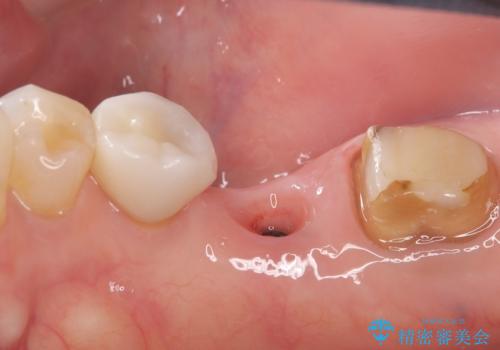

- 主訴:右下のセラミックのブリッジが何度も同じところで折れて壊れてしまう。

対合歯との咬合関係において、右下7番目と6番目の被せものの連結部がたわみやすい環境にあったため、ブリッジの新製ではなくインプラント治療を行いすべての歯を単冠仕上げとすることにしました。

何度も右下6、7間でブリッジが折れてしまうとのことでした。対合歯とブリッジの連結部が強く当たりたわみやすい状態でした。破折しずらい金属を使用したブリッジの選択もありましたが、支台歯(右下7)が失活歯場合、破折リスクが高く、破折してしまった場合にまたブリッジを外しての再治療になってしまう可能性を説明したところ、全て単冠仕上げとできるインプラント治療を希望されました。

右下5番のクラウンは、ブリッジを切断しそのまま使用していただいています。